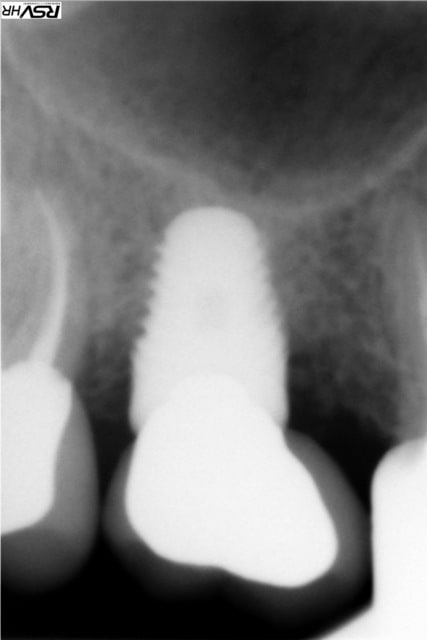

même si je me redirige plutôt vers Zimmer avec une insertion primaire supérieur (à mon avis ) voici un cas de plusieurs années

j'avais gardé une racine distale de 46 (montage 2 ccm soudées au début 4647- avec diastème avec 45 ;2008;le montage

n'a pas tenu longtemps=extraction racine distale et

implantation immédiate legacy2 7 mm(2011)

et ccm transvissée 3 mois après

radio à 2015